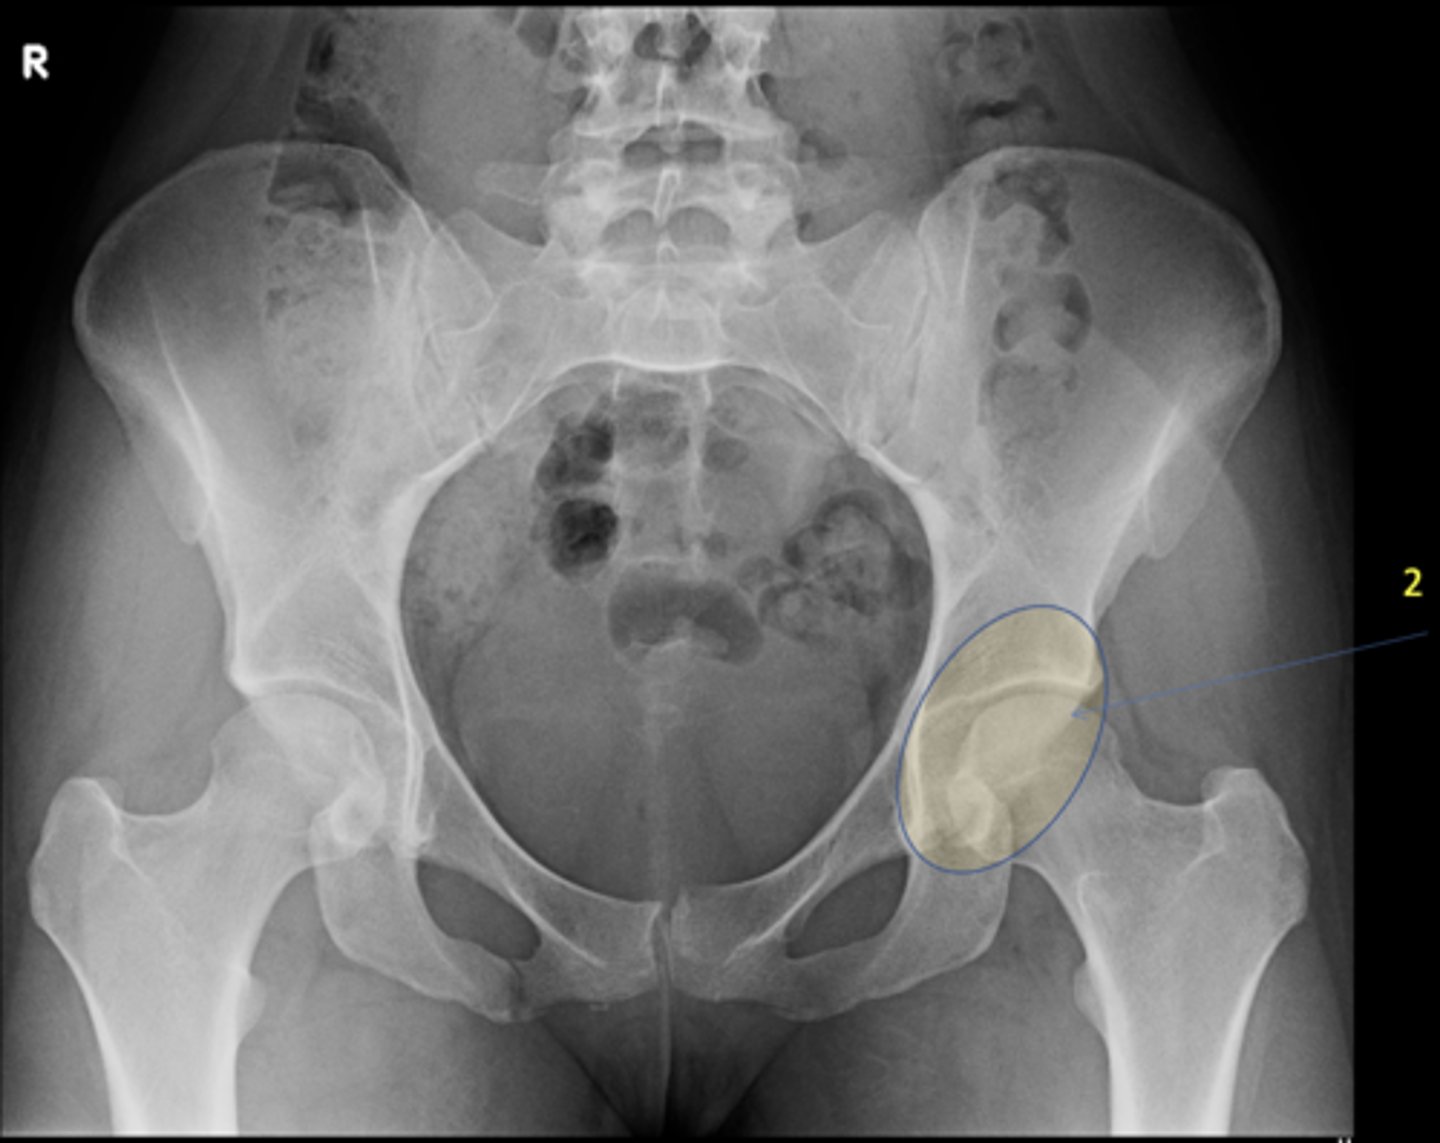

Shenton's line

ID measurement

<p>ID measurement</p>

- AP hip

- AP pelvis

What views are used to see Shenton's line?

<p>What views are used to see Shenton's line?</p>

- Smooth arc along femoral neck

- Obturator foramen

Shenton's line landmarks

<p>Shenton's line landmarks</p>

Continuous and smooth

Shenton's line normal measurements

<p>Shenton's line normal measurements</p>

62

- Hip dislocation

- Femoral neck fracture

- Slipped epiphysis

Clinical significance of Shenton's line

<p>Clinical significance of Shenton's line</p>

Skinner's line

What views are used to see Skinner's line?

<p>What views are used to see Skinner's line?</p>

- Mid-axis of femoral shaft

- Right angle tangent to tip of greater trochanter

Skinner's line landmarks

<p>Skinner's line landmarks</p>

Fovea capitis should lie above or at level of trochanteric line

Skinner's line normal measurement

<p>Skinner's line normal measurement</p>

73

Fracture or other causes of coxa vara

Clinical significance of Skinner's line

<p>Clinical significance of Skinner's line</p>

74

Klein's line

What views are used to see Klein's line?

<p>What views are used to see Klein's line?</p>

Line along femoral neck

Klein's line landmarks

<p>Klein's line landmarks</p>

Line should intersect portion of femoral head

Klein's line normal measurement

<p>Klein's line normal measurement</p>

Slipped capital femoral epiphysis

Clinical significance of Klein's line

<p>Clinical significance of Klein's line</p>